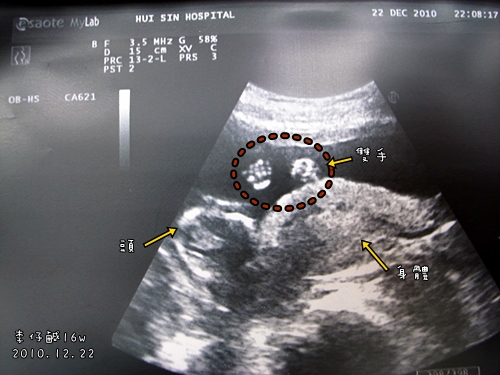

胎兒15週大部分都長怎樣

今天產檢寶寶已經15週了..

可是查了電腦大部分人都說15週已經可以看到五官且腳指頭.還有性別...是真的嗎?

那位何我的寶寶看不到五官..只看到枯爐頭般的骨頭...我ㄧ值注意看有沒有指頭..

都已經放大了卻看到四肢沒看到腳指頭..怎會這樣??

為何我的寶寶為何看不到性別..醫生還說他的腳像美人魚一樣彎曲重疊在一起..